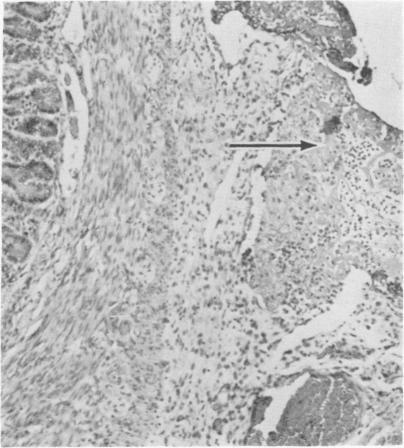

Forty gnotobiotic pigs from six litters were exposed orally to Escherichia coli 083:K.:NM at 69 to 148 hours of age, while 17 pigs from the same litters served as unexposed controls. Clinical signs of infection included fever, anorexia, diarrhea, lameness, and reluctance to move.Eighty-four percent of the exposed pigs in four litters died, while only 13% in two litters died. Gross and microscopic lesions included serofibrinous to fibrinopurulent polyserositis in 96% of the exposed pigs in four litters and 33% of the exposed pigs in two litters. A few pigs had gross and/or microscopic lesions of arthritis. Escherichia coli was routinely isolated from the serous and synovial cavities of infected pigs.Anti-hog cholera serum administered orally as a colostrum substitute gave partial protection against E. coli infection.

来自六窝的40只无菌猪在69至148小时大时经口接触大肠杆菌083:K.:NM,而来自同一窝的17只猪作为未接触的对照。感染的临床症状包括发热、厌食、腹泻、跛行和不愿活动。四窝中84%的接触猪死亡,而两窝中只有13%的猪死亡。大体和显微镜下病变包括四窝中96%的接触猪和两窝中33%的接触猪出现浆液纤维蛋白性至纤维蛋白脓性多浆膜炎。少数猪有关节炎的大体和/或显微镜下病变。从感染猪的浆液和滑膜腔中常规分离出大肠杆菌。口服作为初乳替代品的抗猪霍乱血清对大肠杆菌感染有部分保护作用。